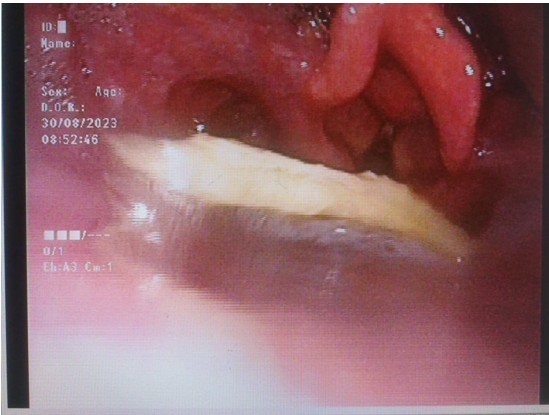

圖片一:電子鼻咽喉鏡顯示方形異物卡在喉咽部